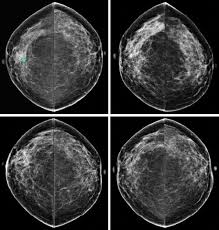

If these tests don't answer the quest. But not every woman who has been diagnosed with breast cancer needs a breast mri. Determining the extent of cancer after a new breast cancer diagnosis. It can also help detect breast cancer in women with breast implants and in younger women who tend to have dense breast tissue. An mri can be used to look for a disease, such as breast cancer. But there are also other reasons to have a breast mri. Inflammatory breast cancer affects breast tissue and can appear unusually dimpled or thick. Breast mri images are combined, using a computer, to create detailed pictures. A waiver of informed consent Mri scan is also used in breast screening for young women who are at higher risk of developing cancer. Dcis on mri may create an area of irregular enhancement of the mri dye into the breast. They're often easy to move around (mobile) and may be tender. A breast mri is a highly effective test.

Lobular breast cancer can be more difficult to see on imaging and scans. Recent research has found that mri can locate some small breast lesions sometimes missed by mammography. Your doctor may recommend a breast mri for the following: The dye collection in the breast can also look clumpy or appear in a section of the breast, depending on the involvement of dcis. Some benign conditions such as fibrocystic disease can look like cancer.

The Radiology Assistant Mri Of The Breast from radiologyassistant.nl Your doctor may recommend a breast mri for the following: A breast mri captures multiple images of your breast. This is why we ask questions about menstrual cycle and hormone therapies prior to your study. What does breast cancer look like on a mammogram? Dcis on mri may create an area of irregular enhancement of the mri dye into the breast. The features of a malignant breast condition on mri scan are often to do with the outer irregular borders of a lesion. An mri can be used to look for a disease, such as breast cancer. If you are at risk of getting a certain disease, your caregiver may want to do an mri to look for signs of the disease.

An mri can help find a disease of the lungs or show tumors (growths) in the chest. But not every woman who has been diagnosed with breast cancer needs a breast mri. The features of a malignant breast condition on mri scan are often to do with the outer irregular borders of a lesion. A rash isn't the only visual symptom of inflammatory breast cancer. Any area that does not look like normal tissue is a possible cause for concern. A breast mri scan might also be used to assess the size of the cancer to check which kind of surgery is possible. They work to destroy the tumor or slow down the growth of cancer cells. This appears most commonly as streaking, known as linear enhancement. On the flip side, there are benign (not cancerous) breast changes which can mimic breast cancer as well. This means that the test finds a mass or other change that seems to show cancer but it is not cancer. Breast mri images are combined, using a computer, to create detailed pictures. What does breast cancer look like on a mammogram? The dye collection in the breast can also look clumpy or appear in a section of the breast, depending on the involvement of dcis.